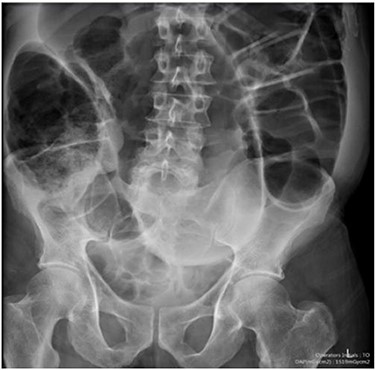

Blood tests on admission were unremarkable, with normal electrolytes levels and lactate. A plain abdominal film showed a typical appearance of caecal volvulus, with an inverted ‘comma sign’ (Fig. 4). A CT scan of the abdomen and pelvis with intravenous contrast was reported as sigmoid volvulus with the involved loops sitting predominantly in the right upper quadrant immediately inferior to the liver (Fig. 5).

Case two: a plain abdominal film showing dilated large bowel and the ‘inverted comma’ sign associated with caecal volvulus.